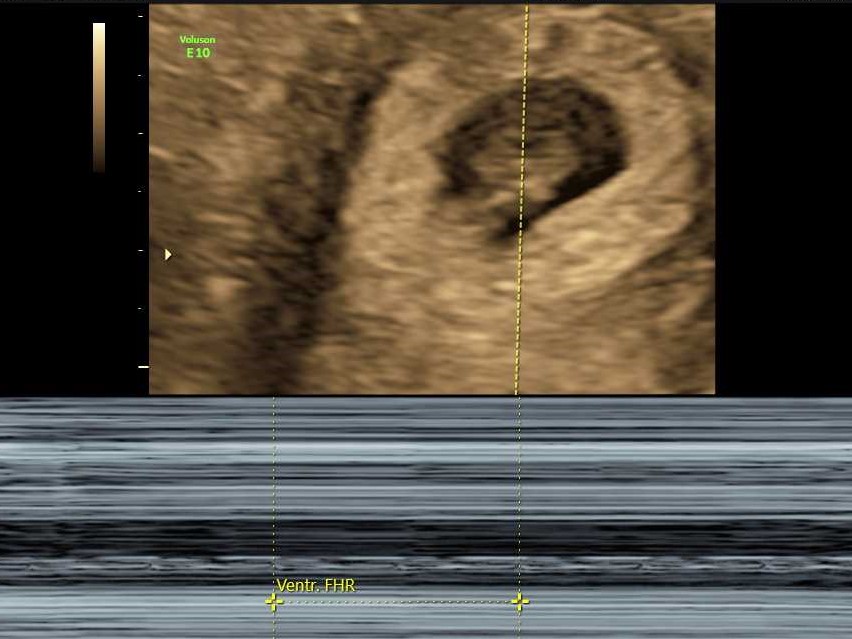

Ultrasound was booked in for Tuesday, which was week 7, day 2, so very early days. Technically a dating ultrasound, but given we knew the conception date, this was to measure and make sure everything was looking good.

I got to see a tiny dot, I guess. There wasn’t much to it. But it was there. I didn’t get to hear a heartbeat, too early for that, but we got to see it, and they could measure it – 146 beats per minute, very good heartrate. And the CRL (which I have just learnt is the “Crown to Rump” measurement) was 1.10cm. Tiny! But it was something.

I know it was still early days, and anything could happen at this stage, but to know there was something there was very cool. And to get some photos for my records.